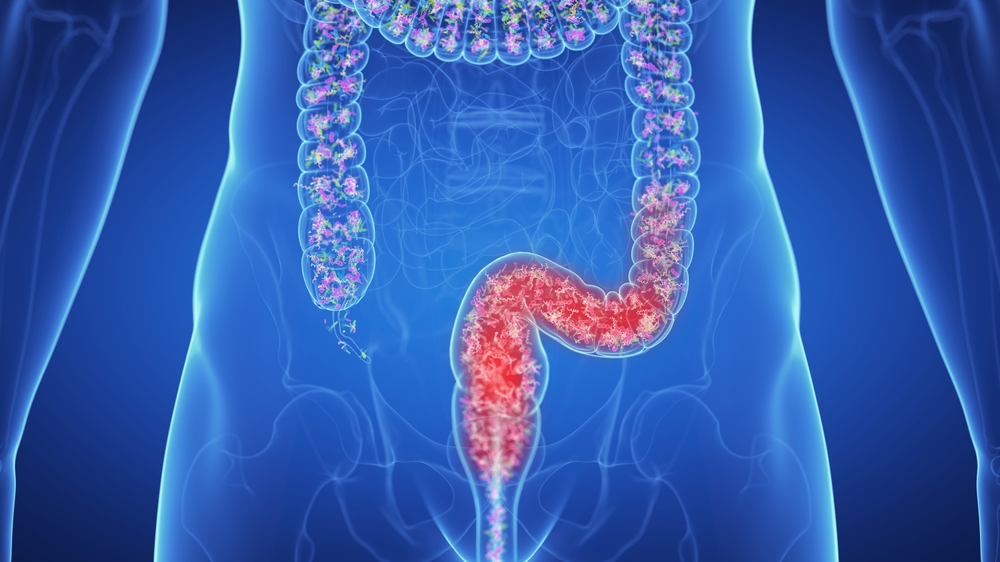

۳. انسداد روده

در موارد شدید، مدفوع فشرده و خشک ممکن است راه خروجی روده را مسدود کند. این وضعیت که به آن «انسداد مدفوعی» گفته میشود، میتواند نیازمند مداخلات پزشکی فوری مانند تنقیه یا حتی جراحی باشد.

این نشانهها میتوانند زنگ خطری برای وجود مشکلات گوارشی عمیقتر، مثل سندرم روده تحریکپذیر (IBS) یا حتی انسداد روده باشند. در برخی موارد، یبوست طولانیمدت ممکن است باعث افزایش سموم در بدن، افت عملکرد کبد و اختلال در جذب مواد مغذی شود.

- بیماریهایی مثل سندرم روده تحریکپذیر، دیابت، کمکاری تیروئید و انسدادهای مکانیکی روده نیز از عوامل بروز یبوست مزمن هستند.